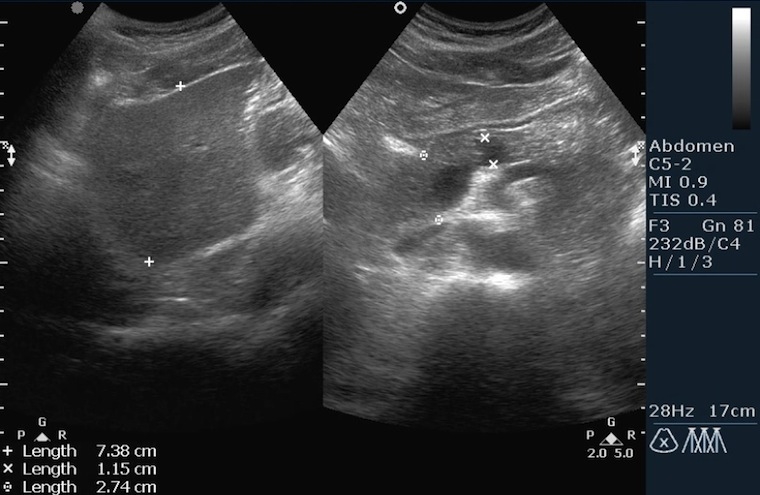

УЗИ диагностика кольцевидной поджелудочной железы: что важно знать